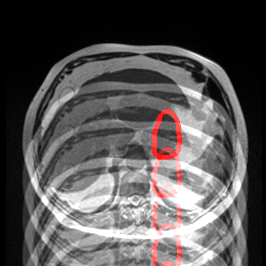

Object Rotation

X-ray GMAIMMbench Disease Diagnosis

Object Rotation - L0 (Original)

L0

L0 (Original)

Object Rotation - L1 (Moderate)

L1

L1 (Moderate)

Object Rotation - L2 (Severe)

L2

L2 (Severe)

Question

Given the boxed region in the X-ray image, which abnormality is the image most indicative of?

A pneumothorax B pulmonary fibrosis C bone fracture D pleural effusion

Ground Truth: A. pneumothorax